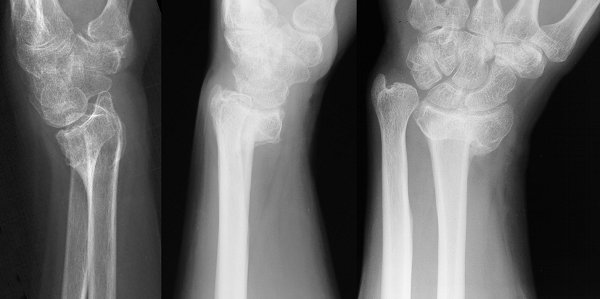

Figure Legend:

Distal radius malunions are common after closed reduction of an

unstable fracture pattern, resulting in dorsal (left) or volar (center)

angulation, shortening and loss of radial inclination (left).

Functional outcome correlates poorly with radiographic changes.